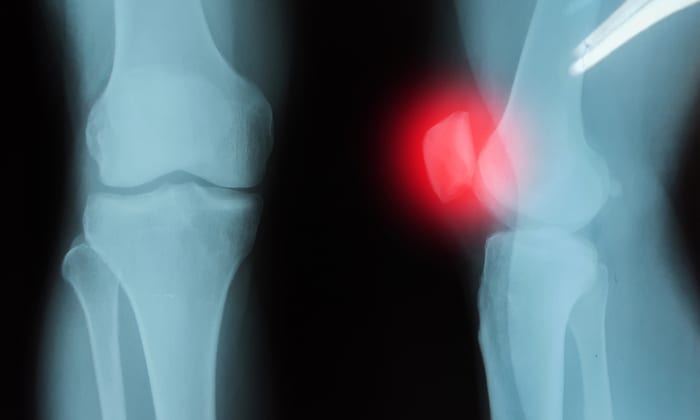

ข้ออักเสบจากการติดเชื้อ  (Septic Arthritis)  คือการติดเชื้อในข้อต่อ เกิดขึ้นเมื่อเชื้อแบคทีเรียหรือเชื้อไวรัสแพร่กระจายผ่านกระแสเลือดไปยังบริเวณข้อต่อหรือของเหลวรอบ ๆ ข้อต่อ ที่เรียกว่า น้ำไขข้อ การติดเชื้อมักเริ่มต้นที่บริเวณส่วนอื่น ๆ ของร่างกาย และแพร่กระจายผ่านทางเลือดไปยังเนื้อเยื่อข้อต่อ

ข้ออักเสบจากการติดเชื้อ  (Septic Arthritis)  คือการติดเชื้อในข้อต่อ เกิดขึ้นเมื่อเชื้อแบคทีเรียหรือเชื้อไวรัสแพร่กระจายผ่านกระแสเลือดไปยังบริเวณข้อต่อหรือของเหลวรอบๆ ข้อต่อ ที่เรียกว่า น้ำไขข้อ การติดเชื้อมักเริ่มต้นที่บริเวณส่วนอื่น ๆของร่างกาย และแพร่กระจายผ่านทางเลือดไปยังเนื้อเยื่อข้อต่อ

อย่างไรก็ตามข้ออักเสบจากการติดเชื้อ  อาจเกิดจากการได้รับบาดเจ็บบริเวณข้อต่อทำให้เชื้อโรคเข้าสู่ข้อต่อโดยตรง ส่งผลให้ผู้ป่วย มีอาการปวดบวมบริเวณข้อต่อ มีไข้ รู้สึกอ่อนเพลีย เหนื่อยล้า

• ทดสอบโดยภาพ การทดสอบเหล่านี้จะช่วยให้แพทย์เห็นตำแหน่งความผิดปกติได้ชัดเจนขึ้น เช่น การเอกซเรย์ (X-Ray) ตรวจวินิจฉัยโรคด้วยคลื่นแม่เหล็กไฟฟ้า (Magnetic Resonance Imaging : MRI) การตรวจวินิจฉัยโรคด้วยเครื่องเอกซเรย์คอมพิวเตอร์ (Computerized Tomography Scan : CT SCAN)  เวชศาสตร์นิวเคลียร์ (Nuclear scans)